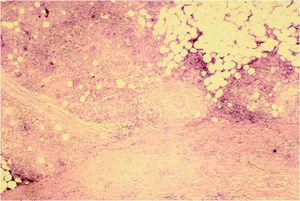

Se realizó una biopsia profunda cuyo estudio histopatológico mostró epidermis y dermis papilar normales. En la dermis profunda y grasa subcutánea se apreciaban granulomas constituidos por células gigantes multinucleadas e histiocitos; algunas células gigantes contenían una vacuola con un cuerpo asteroide en su interior. En la zona subcutánea, estos granulomas afectaban principalmente a los lobulillos grasos, alguno de los cuales estaba completamente sustituido por dichas formaciones (fig. 2). Las tinciones con ácido peryódico de Schiff (PAS) y de Ziehl-Neelsen fueron negativas. El examen con luz polarizada descartó la presencia de cuerpos extraños. El cultivo en medio Löwenstein-Jensen fue negativo.

Fig. 2.--Dermis reticular profunda y grasa. Se aprecian granulomas con células multinucleadas e histiocitos.